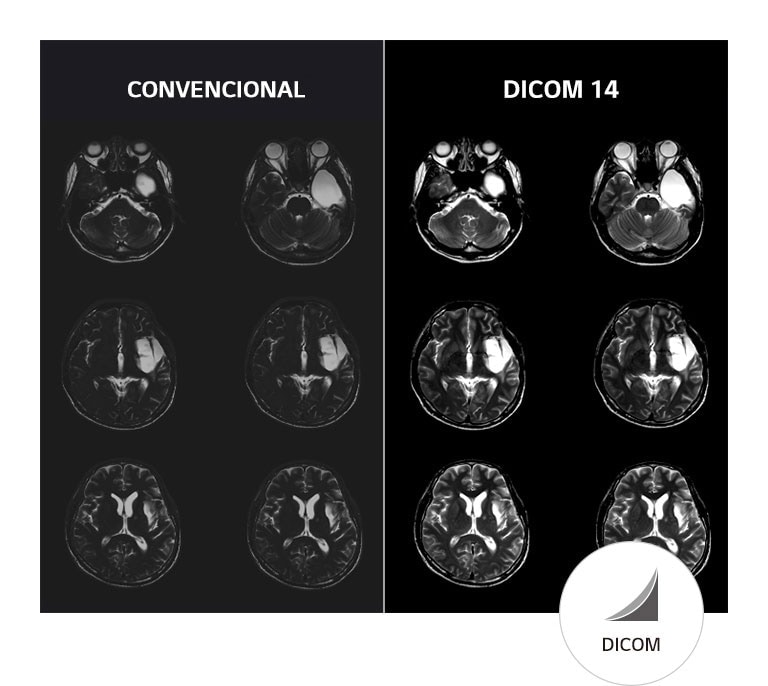

Imágenes Médicas con Consistencia Asegurada

Compatible con DICOM

SIM